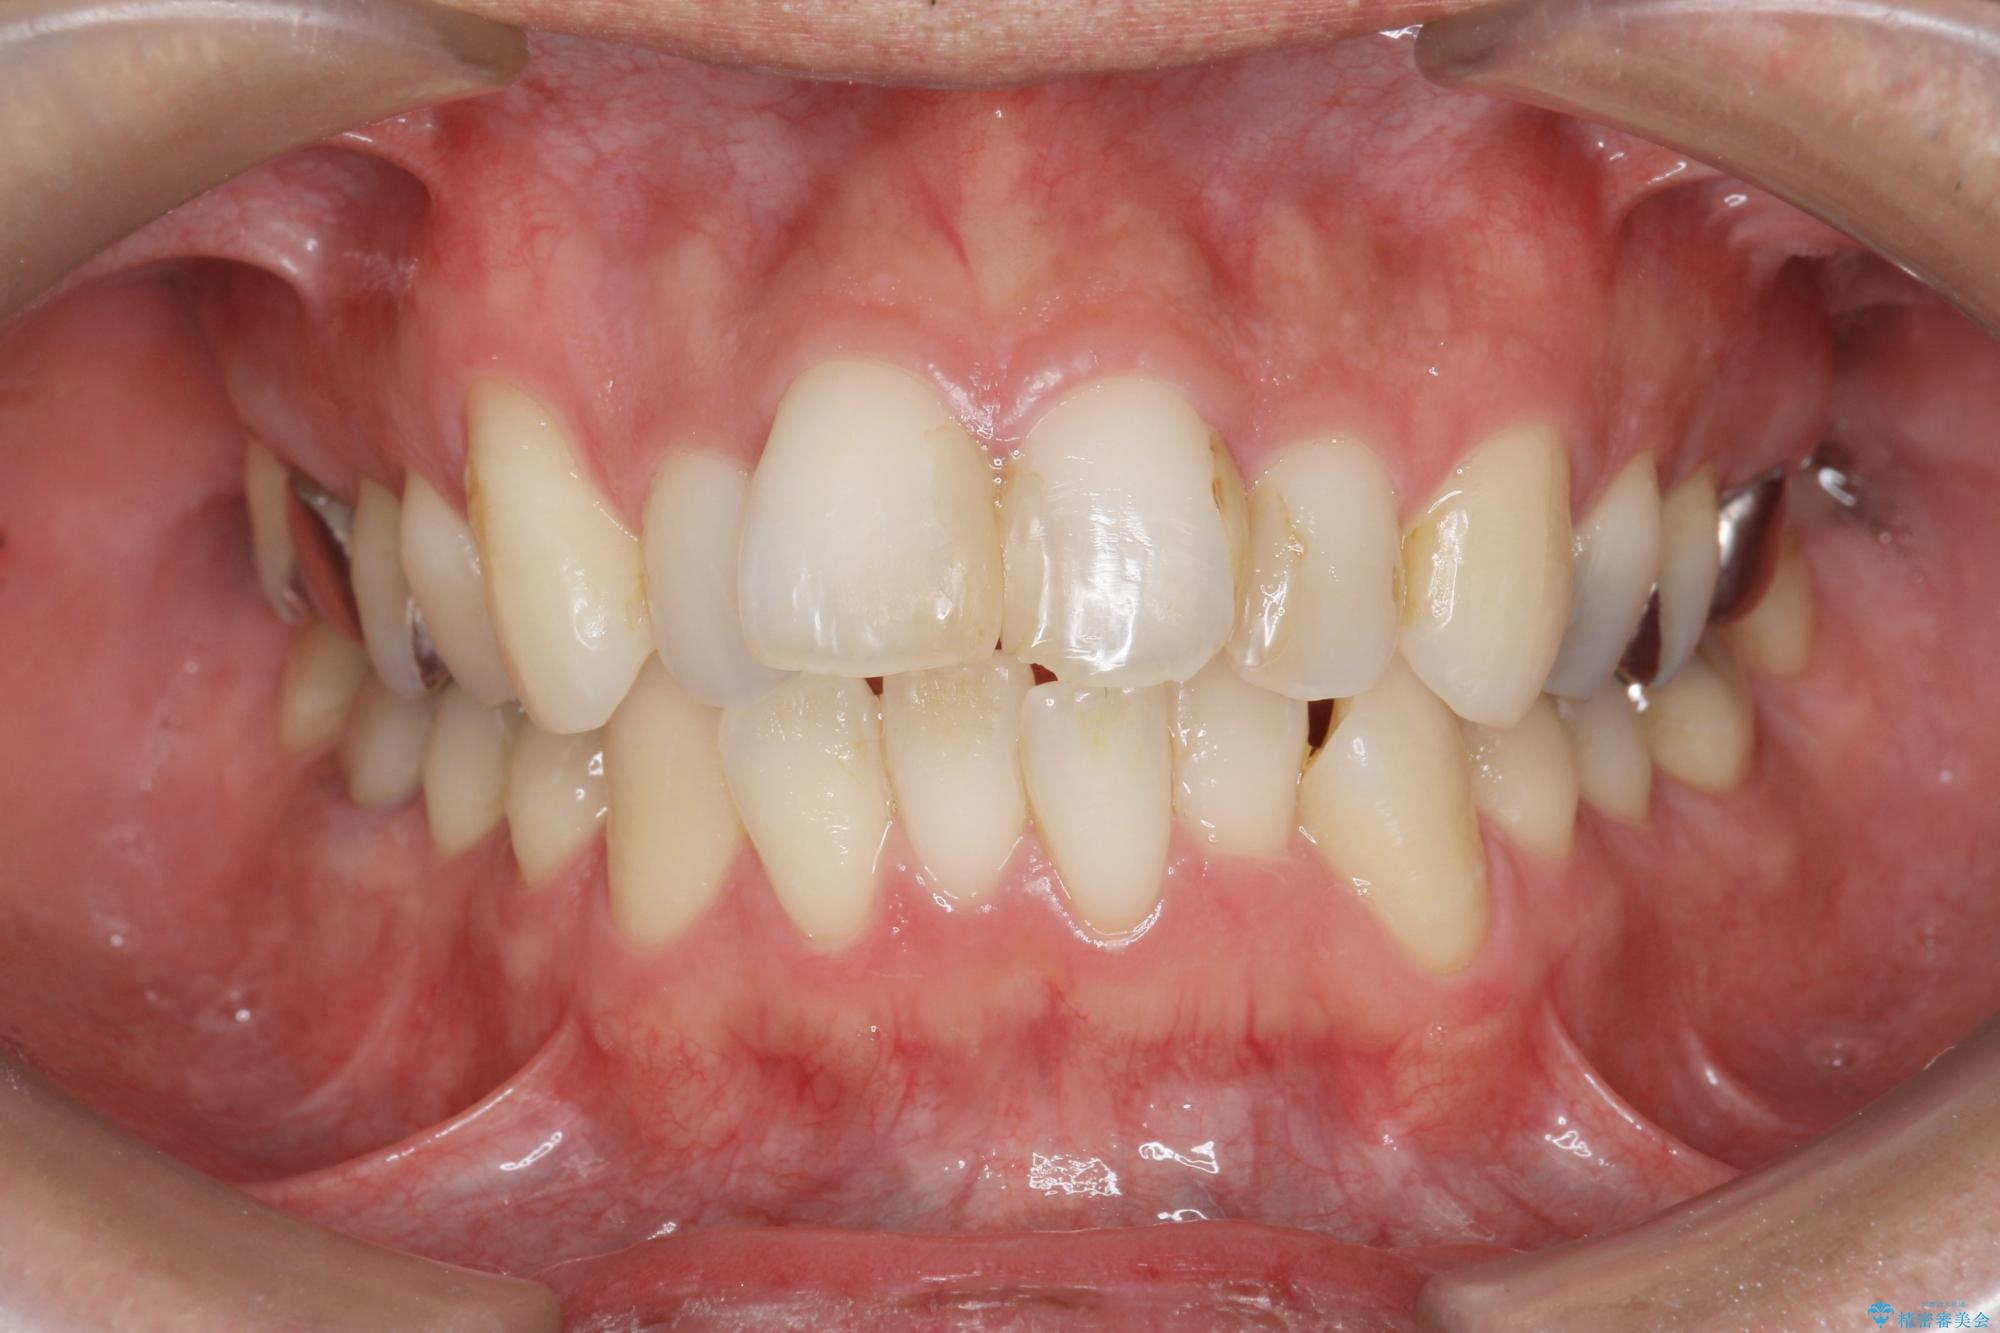

- 突き出た前歯の角度の改善と虫歯治療の改善を求めて来院されました。

虫歯を除去したのち、マウスピース矯正治療を行い、歯並びやがたつきを改善したのち、セラミックに置き換えることで審美性の向上を計画します。